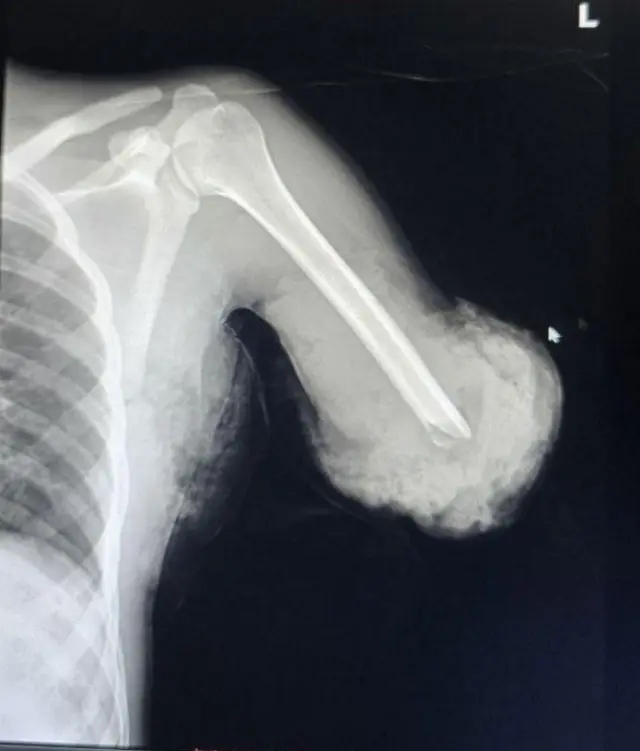

ኣብ ኢትዮጵያ ብሓደጋ ምሉእ ብምሉእ ዝተቘርጸ ኢድ ዳግማይ ብዕውት መንገዲ ከምዝተተኸለ ተገሊጹ።

ወዲ 20 ዓመት መንእሰይ ቅድሚ ሰለስተ ሰሙን ቅልጽሙ ኣብ ማሽን ዕንጸይቲ እናሰርሐ እንከሎ ብዘጋጠሞ ሓደጋ እዩ ተቘሪጹ።

"ኣብ ቅልጽሙ ማለት ካብ ኩርናዕ ኢዱ ቅሩብ ልዕል ኢልካ እዩ ተቘሪጹ፣ በቃ ምሉእ ብምሉእ ኢዱ ተፈላልዩ እዩ መጺኡና" ይብል ዶክተር ኣንተነህ።

ድሕሪ እቲ ዘስካሕክሕ ሓደጋ ናብ ሕክምናዊ ትካል ዝተወስደ እቲ መንእሰይ፡ ኢዱ ዳግማይ ንምትካል ዝተግበረ መስርሕ ኣዝዩ ከቢድን ዝተሓላለኸን ከምዝነበረ እውን ጠቒሱ።

እቲ ኦፕሬሽን ኣብ ክልተ እብረ እዩ ተኻይዱ።

እቲ ቀዳማይ ከባቢ 6 ሰዓታት ወሲዱ። ድሕሪ ክልተ ሰሙን ድማ እቲ ካልኣይ መብጣሕቲ ተኸይዱ።

ዶክተር ኣንተነህ እቲ ካልኣይ መስርሕ እውን 6 ሰዓት ከምዝወሰደን ናይ መወዳእታ እዩ ኢሎም ከምዝኣምኑን ይዛረብ።

ኣብ እዋን መብጣሕቲ "ቀዳምነት ንዓጽምን ሰራውር ደምን ተዋሂቡ፣ እቲ ዝተቘርጸ መሓውር ንኸይመውት ድማ ሰራውር ደም ዳግማይ ክተኣሳሰር ተገይሩ። ሰራውር ደምን ዓጽምን ኣብ ቦታኦም ምስ ተመልሱ፡ እቶም መትኒታትን ልጋማትን ግዜ ክወሃቦምን እቲ መብጣሕቲ ብደረጃታት ክካየድን ወሲኖም" ኢሉ።

ዝተቘርጸ ዓጽሚ ዳግማይ ብምትካል ክሓዊ ምግባር ከምዝኽእል ዝገለጸ ዶክተር ኣንተነህ፡ እቲ ዝተቘርጸ ክፋል መግቢ ምእንቲ ክረክብ፡ ሰራውር ደም ዳግማይ ክተኣሳሰሩ ከምዘለዎም ገሊጹ።

"ኣብዚ ሕጂ ሰዓት ኢዱ ምሉእ ብምሉእ ኣብ ጽቡቕ ኵነታት እዩ ዘሎ። ይኵን እምበር ኣእዳዉ ንምንቅስቓስ ፊዝዮ ተራፒን ካልኦት ሕክምናዊ ክንክንን ከድልዮ እዩ።ንሕናውን ውጽኢታዊ መፈጸምታ እና ንጽበ።"

ዶክተር ኣንተነህ፡ ከም ምንቅስቓስ ዝኣመሰለ ፊዚዮቴራፒ (ሕክምና ተሃድሶ) ድሕሪ ምግባር፡ ኢድ እቲ ከምቲ ቅድሚ ሕጂ ዝነበረ ጽቡቕ ምንቅስቓስ ክገብር ከምዝኽእል ይዛረብ።